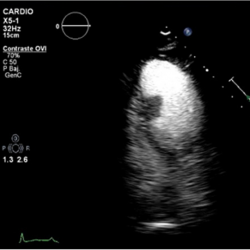

Figure 4.

3D-Zoom. Detailed view of the mass.